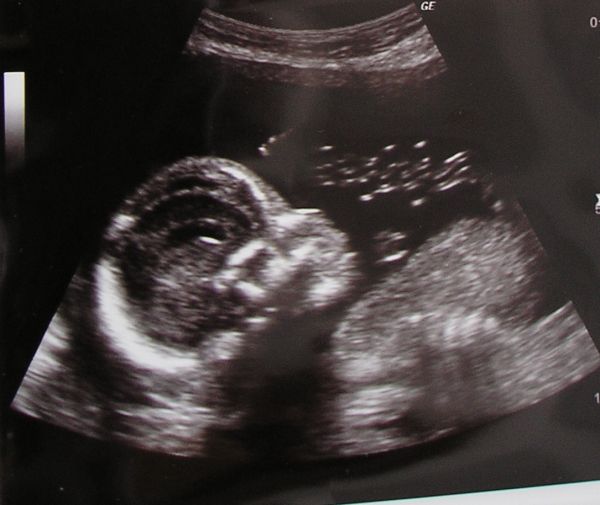

Helyes a lánykád az UH fotón, s tényleg hasonlit a bátyjára. Nagyon jó az összebújós fotó, és a tigrises felső is